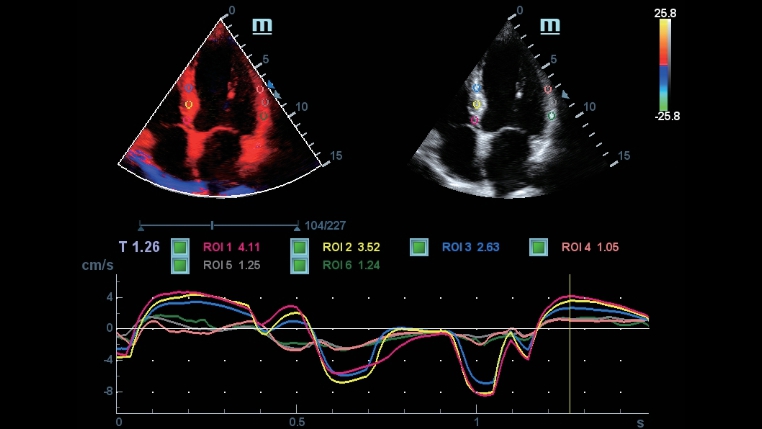

DC-40 con Full HD ofrece una gama de herramientas que maximizan la precisiĂłn del diagnĂłstico con comodidad. DC-40 con Full HD le brinda una soluciĂłn completa para aplicaciones clĂnicas convencionales, con un flujo de trabajo simplificado que garantiza la eficiencia y permite realizar escaneos generales, de ginecologĂa, obstetricia y cardiologĂa.

Smart Track

Smart Track proporciona una optimizaciĂłn rĂĄpida e inteligente de imĂĄgenes vasculares con un sencillo manejo de un solo toque. Puede optimizar el espectro de Color, Potencia y PW mediante seguimiento automĂĄtico y reducir pasos que llevan tiempo. Por lo tanto, el flujo de trabajo del examen vascular se simplifica con una Ăłptima visualizaciĂłn.